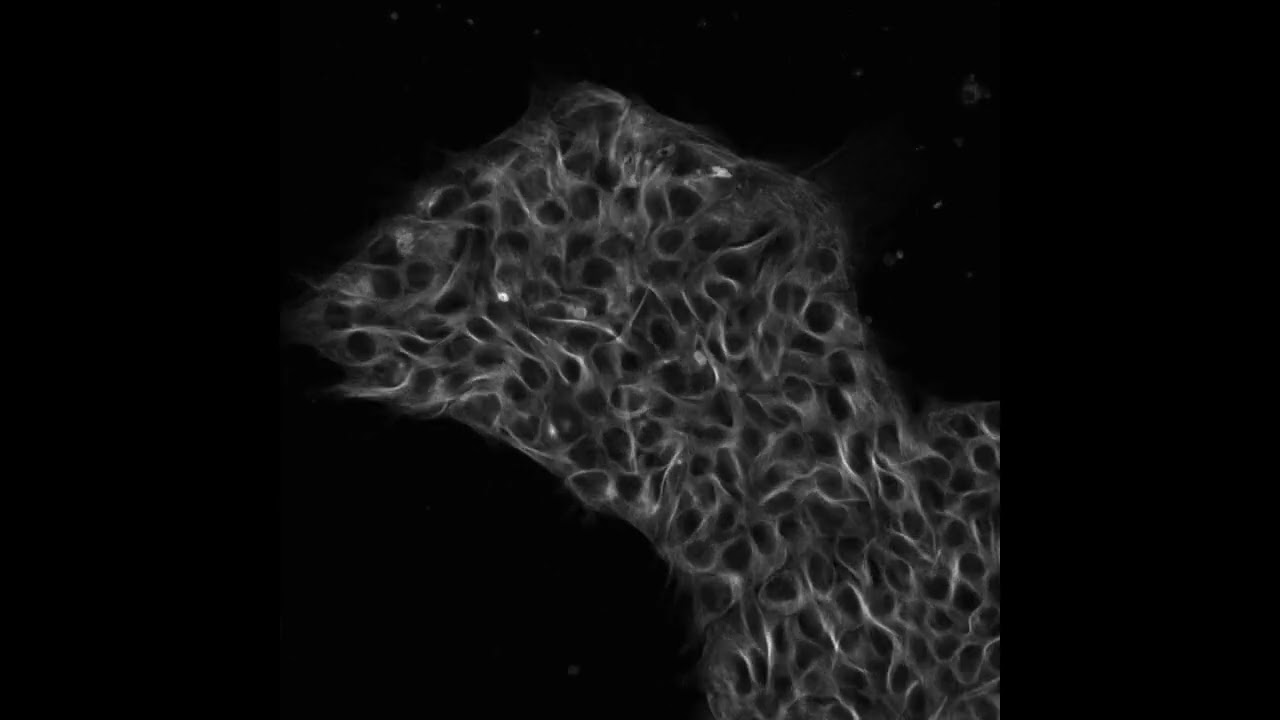

Human Skin Cell Under Microscope Labeled The skin under a light microscope comprises two distinct layers epidermis and dermis. learn the skin microscope with a labeled diagram. Image of the cells of the epidermis. the cells were labelled with tags that glow under the light of a special microscope. the white colour has tagged the nucleus of each cell, the red identifies a protein.